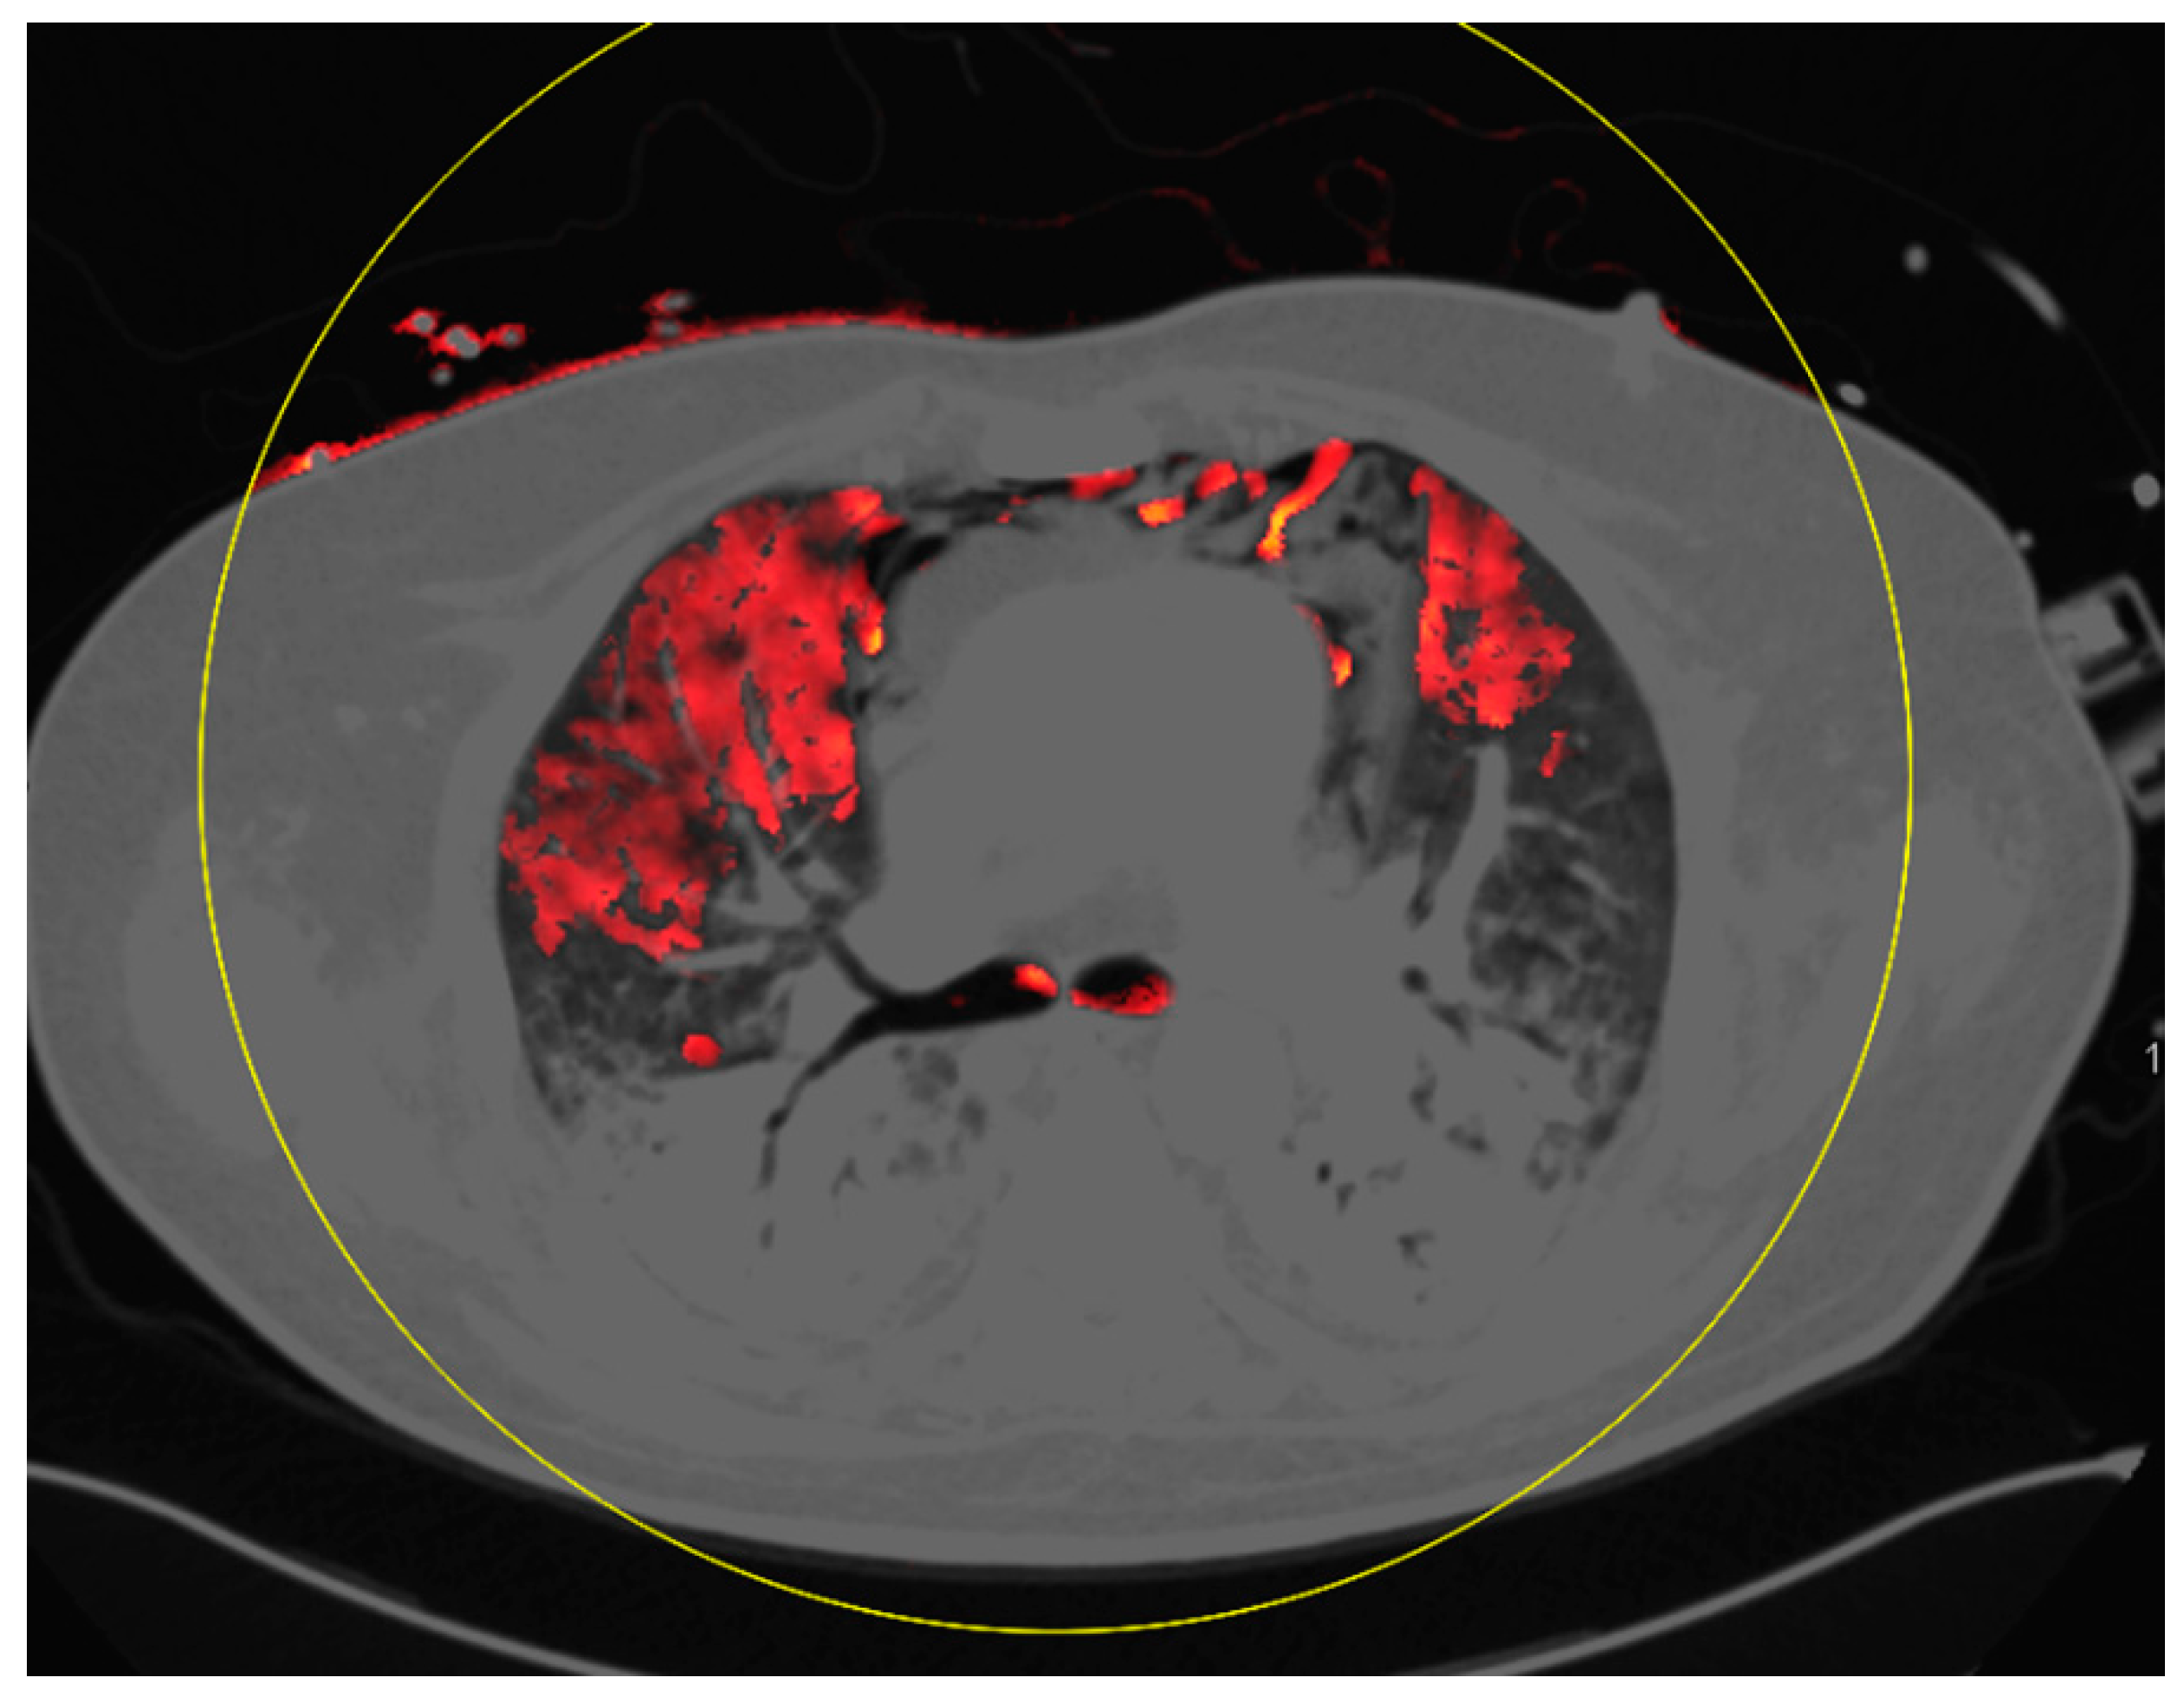

4. Discussion